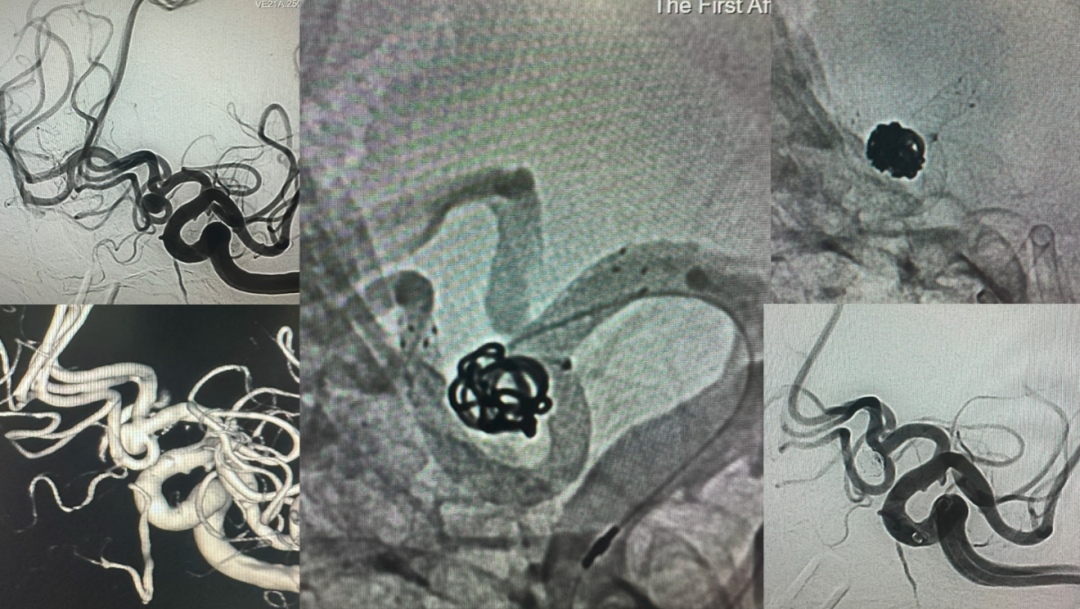

患者为 65 岁中年女性,在外院体检,行头颅 MRA 后提示前交通动脉瘤。为求进一步治疗慕名来到交大一附院就诊,以「前交通动脉瘤」收住神经内科。患者入院后,积极完善术前相关检查,排除手术禁忌后行全脑血管造影,进一步明确前交通动脉瘤诊断,瘤体高 4.8 mm,瘤体宽 4.2 mm,瘤颈 4.0 mm。韩建峰教授、于嘉教授团队综合考虑患者年龄,动脉瘤大小,动脉瘤位置以及形态等相关因素后,建议积极介入干预以预防动脉瘤破裂造成生命危险。

手术的关键点在于患者载瘤动脉纤细迂曲,左侧大脑前动脉 A2 段(计划的支架远端锚定点)直径约 1.5 mm,左侧大脑前动脉 A1 段(计划的支架近端锚定点)直径约 2.5 mm,常规的编织支架置入在不足 2 mm 的血管内再闭塞率较高,而且在较为迂曲的血管内释放支架有贴壁不良导致血管闭塞的风险,开环薄壁支架可以较好的在迂曲纤细的血管里打开,但是支架网孔较大,阻挡弹簧圈的效果不佳。在韩建峰教授、于嘉教授主持下,经全科讨论拟用 LVIS EVO 这一新型编织支架辅助完成前交通动脉瘤栓塞。

患者及家属同意手术后,并经过详细的术前检查、谨慎的术前讨论及完善的药物准备后,由韩建峰教授及于嘉教授带领团队成员孙鹏、宋文峰和陈晨等医生,在麻醉手术部及介入手术室的大力支持和通力配合下,全麻为该患者实施了 LVIS EVO 支架辅助前交通动脉瘤栓塞术,手术过程顺利、术后患者转入神经内科监护室密切观察,次日转回普通病房。